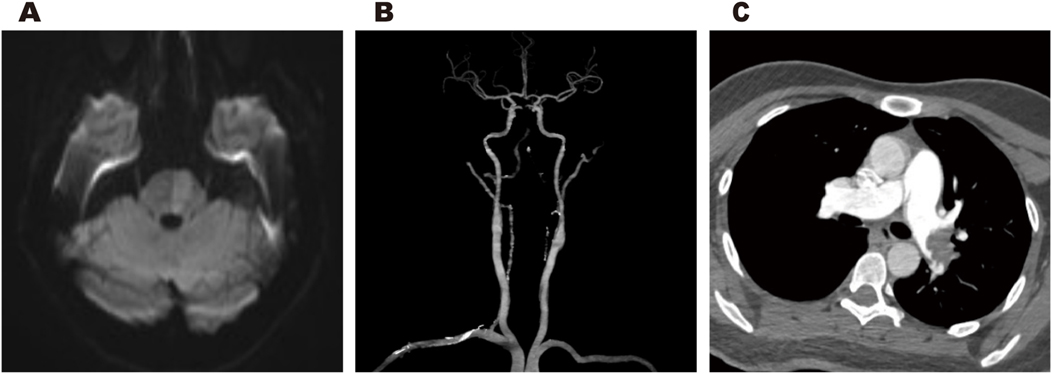

Cranial magnetic resonance imaging (MRI) revealed an acute pontine infarction (Figure 1A). Head and neck computed tomography angiography (CTA) showed basilar artery occlusion (Figure 1B) and incidentally detected left pulmonary artery embolism (Figure 1C), suggesting the possibility of multisystem embolism. Further digital subtraction angiography (DSA) of the whole brain confirmed interruption of blood flow in the distal basilar artery (Figure 2A). Pulmonary angiography revealed left pulmonary artery embolism (Figure 2B). Antegrade venography of the lower extremity deep veins showed bilateral iliac vein thrombosis (Figures 2C,D). The patient underwent emergency mechanical thrombectomy of the basilar artery and placement of an inferior vena cava filter (Figure 3B). Post-operatively, imaging evaluation showed the basilar artery was patent (Figure 3A), and the patient was transferred to the neurology department for further treatment.

Figure 1

Cranial MRI revealed an acute pontine infarction (A). Head and neck CTA revealed basilar artery occlusion (B), and incidentally showed left pulmonary artery embolism (C).

Figure 3

Post-thrombectomy imaging revealed normal anterograde blood flow in the basilar artery (A). Postoperative changes following inferior vena cava filter implantation (B). Post-procedural imaging revealed appropriate positioning of the PFO closure device (C).